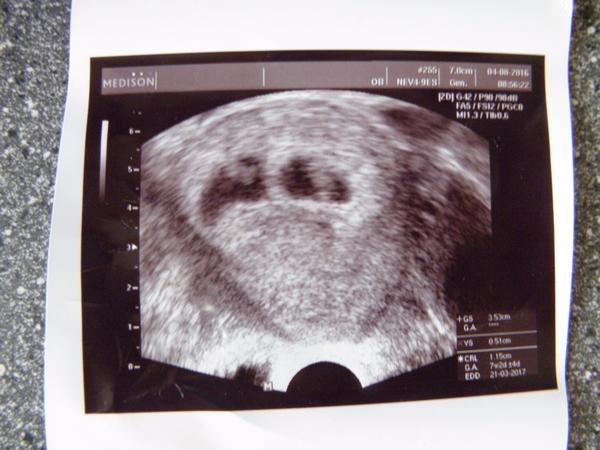

Jinak já jsem po 1. IVF, už 7. den od ET jsem měla //, minulý týden na UTZ potvrzeny dvě bublinky, dneska jsem 5tt+4 a už se do ničeho nevejdu - mám dojem, že s dvojčátkama bude všechno mnohem intenzivnější a rychlejší 😀

@adusee Já byla na první kontrole až 9 tt+1, a bylo krásně slyšet i srdíčko, ale doktor nepoznal nic. Akorát říkal, že už to je dost velké, ale asi tím myslel, že mu tam chodí maminky hned v 6. týdnech. Já jsem neměla kam spěchat. A pak jsem ve 13. týdnu začala krvácet, a můj doktor měl dovolenou, tak jsem jela do nemocnice a doktor mi říkal, že tam jsou 2. K mému doktorovi jsem pak šla za 10 dní na objednaný termín kontroly a divil se. Oni byli schovaní za sebou.